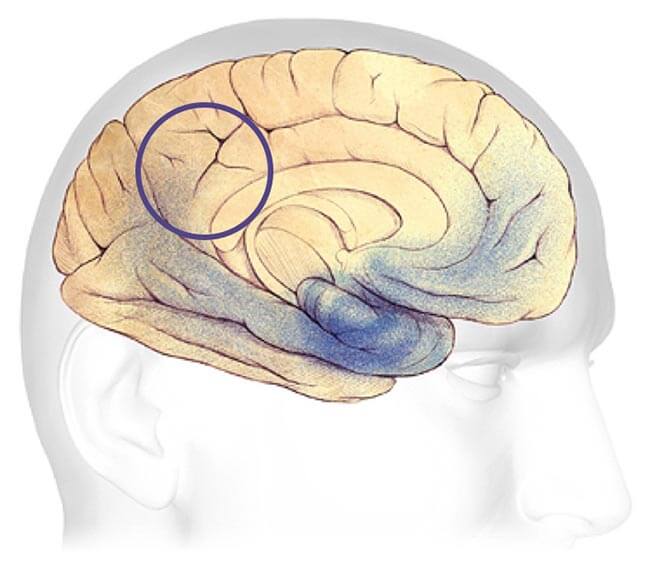

Progression Through the Brain

Plaques and tangles (shown in the blue-shaded areas) tend to spread through the cortex in a predictable pattern as Alzheimer's disease progresses. The rate of progression varies greatly. On average, a person with Alzheimer's lives four to eight years after diagnosis, but can live as long as 20 years, depending on other factors. The course of the disease depends in part on age at diagnosis and whether a person has other health conditions.

Earliest Alzheimer's - changes may begin 20 years or more before diagnosis.

Earliest Alzheimer's Stages

In the earliest stages, before symptoms can be detected with current tests, plaques and tangles begin to form in brain areas involved in:

Learning and Memory

Thinking and Planning